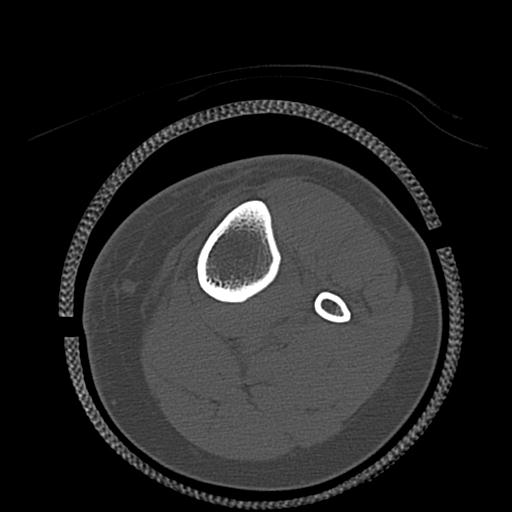

49554 3/13 膝 4R 3/16 4R 1/18 2R 78歳男性 膝蓋骨骨折